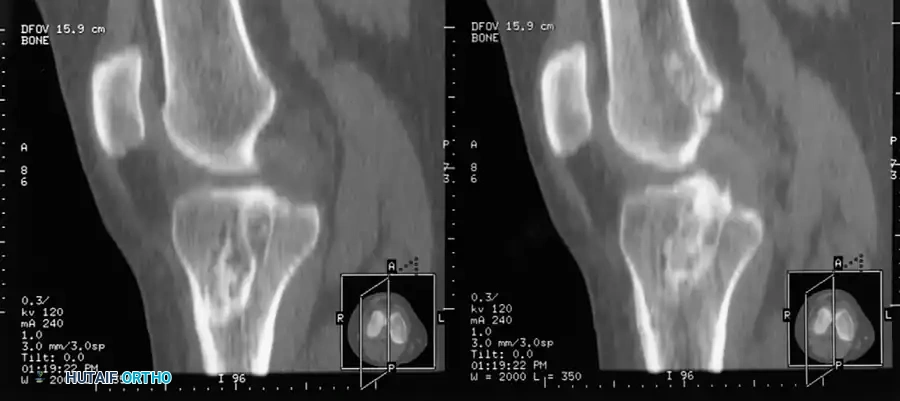

Magnetic Resonance Imaging (MRI):

MRI is the gold standard advanced imaging modality, with reported accuracies approaching 95% to 100%. Because the ACL courses obliquely, standard orthogonal sagittal planes may not capture the entire ligament.

RADIOGRAPHIC PEARL: Utilizing a nonorthogonal plane—achieved by externally rotating the knee approximately 15 degrees during the scan—allows for visualization of the entire ACL in a single continuous frame.

MRI is also highly sensitive for detecting associated bone bruises (microtrabecular fractures), which occur in up to 80% of acute ACL tears. These are typically located on the lateral femoral condyle and the posterolateral tibial plateau, reflecting the footprint of the pivot-shift mechanism.

Image

Fig. 43-102 Magnetic resonance image shows bone bruise after anterior cruciate ligament tear.